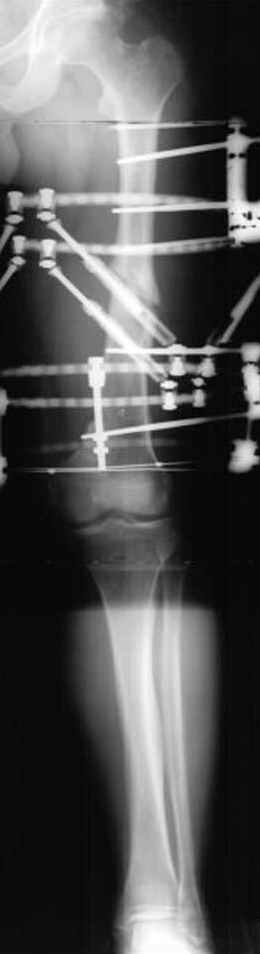

Отправитель: Djoldas Kuldjanov 23 Ноябрь 2004, 18:21

пластическая модель; и коррекция бедра аппаратом Илизарова.

Имею другие снимки тоже, получится как отчет о моей работе.

Узкий к-м канал - тонкий гвоздь- усталостный перелом дистальных винтов - развитие нестабильности и как ее результат остеолиз вокруг гвоздя - деформация анатомической оси бедра. Похоже, что я понял почему аппарат, а не новый гвоздь:-)